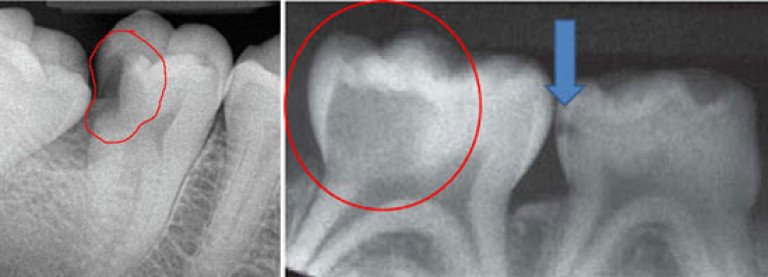

Рис.1 контактные кариозные полости.

Так как эмаль- самая сильная часть зуба, нарушения происходят в ее структуре. Но сам кариес развивается в дентине(следующий слой после эмали). Это значит, что пока кариес не заметен визуально. Как только кариозный процесс станет большим, эмаль не выдержит и провалиться. Так визуально будет видна кариозная полость.